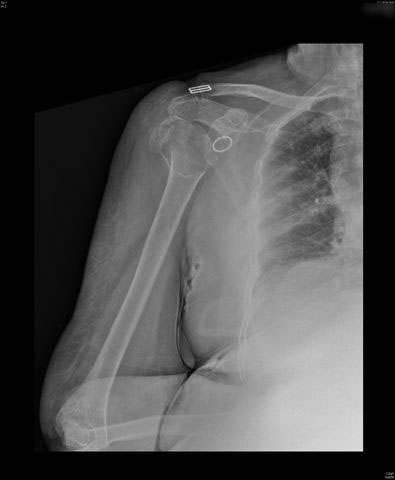

Fractura subcapital de húmero.